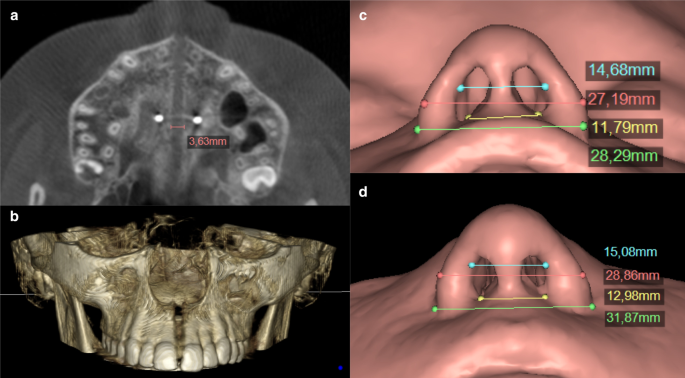

鼻上顎複合體:鼻腔與口腔,是樓上與樓下

要理解上顎擴弓,家長可以把口腔和鼻腔想像成一樓和二樓,而上顎骨就是天花板。這個結構醫學上稱為鼻上顎複合體(Nasomaxillary Complex)。它不只影響牙齒排列的空間,也影響鼻腔底部的寬度。所以,當上顎太窄時,不只是牙齒沒地方排,鼻腔空間也可能跟著受限。這會造成鼻呼吸阻力很大,進而形成習慣性口呼吸。而當上顎擴弓把骨縫打開時,不只為牙齒創造空間,也能讓鼻呼吸變得順暢。這也是為什麼許多家長一開始只是因為孩子牙齒不整齊來評估,後來卻發現:孩子真正需要的不只是齒列,還有呼吸道空間。這一點也是大部分牙齒矯正醫師忽略的環節。

3. 為鼻腔與呼吸道創造較好的條件

上顎擴弓雖不是治療所有呼吸問題的萬靈丹,但對許多孩子來說,上顎與鼻腔空間改善後,鼻子過敏與鼻塞問題也可能隨之改善。

3. 鼻子更通,呼吸更順

對部分孩子而言,擴弓後可能觀察到:

- 鼻呼吸變得較順

- 睡覺張口減少

- 打鼾改善

- 起床口乾減少

- 白天活動較不容易喘